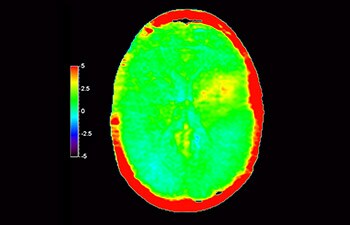

Numa sociedade em que os distúrbios neurológicos representam um fardo pesado a Philips está empenhada em proporcionar uma excelente clareza de diagnóstico e orientação de tratamentos para todos os pacientes. Atualmente embora a RM seja o padrão de excelência na imagiologia neuro-oncológica a sua precisão na classificação de tumores e avaliação de acompanhamento de tratamentos pode ser melhorada. O 3D APT (Amide Proton Transfer) é um método de imagem cerebral por RM único e sem contraste que responde à necessidade de um diagnóstico mais confiante em neuro-oncologia. O 3D APT utiliza a presença de proteínas celulares endógenas para produzir um sinal de RM que se correlaciona diretamente com a proliferação celular um indicador de atividade tumoral. O 3D APT pode auxiliar os profissionais de saúde qualificados na diferenciação entre gliomas de baixo e de alto grau e na diferenciação entre progressão tumoral e efeito do tratamento1.